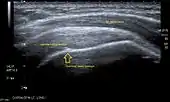

Longitudinal ultra sonography of the supraspinatus tendon